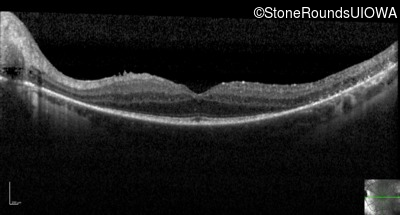

Optical Coherence Tomography - Left - 20/32 -2

Exemplar / OCT Stack

OCT Stack